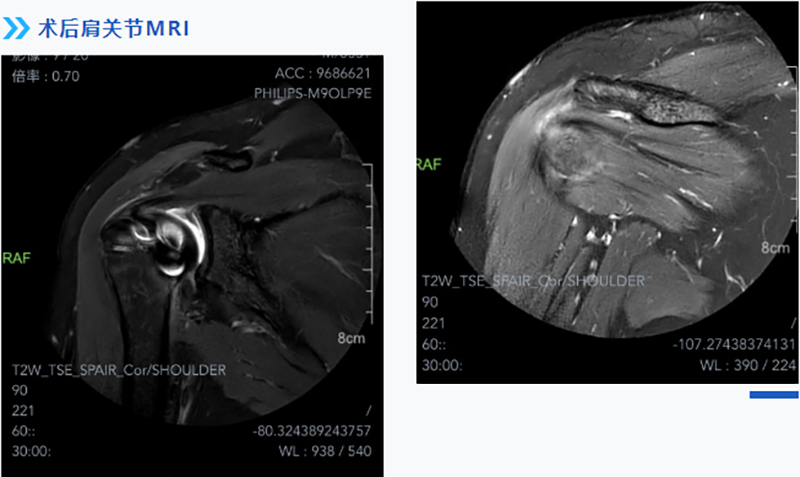

無需“大刀闊斧” !柳人醫運動醫學科應用關節鏡微創技術治療巨大肩袖撕裂

考慮到患者對術后功能期望值較高,術中對于如何將撕裂的肌腱完全恢復如初等因素充滿了挑戰。經過充分的術前準備,運動醫學科團隊應用關節鏡下微創技術,根據術中實際情況,精準植入縫合錨釘,將撕裂的肩袖縫合回原本的位置,恢復其原本具有的功能,被牽拉的腋神經也得到了松解,術后患者患肢疼痛、麻木的癥狀立即得到了緩解。

術后3個月,患者門診復查時,肩關節功能開始逐步恢復,已經能自己抬得起手,肩膀麻木的癥狀也沒有了,患者對治療效果表示非常滿意。